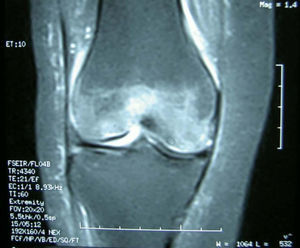

Pruebas complementarias. El estudio radiológico inicial mostró una radiolucencia difusa de la metáfisis y la epífisis femoral distal, sin líneas de fractura; el espacio articular permanecía normal (fig. 1). La resonancia magnética (RM) mostraba un extenso edema óseo en la epífisis femoral distal, más marcado en cóndilo externo, con disminución de la señal en T1 y aumento en T2, además de un pequeño derrame articular difuso (fig. 2).